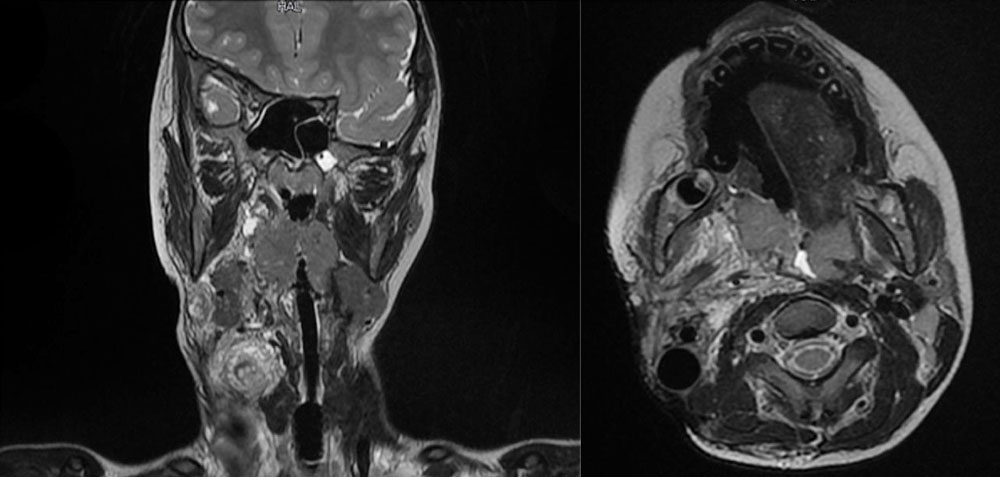

Extensive arteriovenous malformation of the orbit and surrounding facial skin

In this example an arteriovenous malformation is described, which was treated several times interventionally with EVOH and pharmacologically with sirolimus before surgical treatment. Complications such as profuse bleeding from the orbit, repeated bacterial infections as well as the disastrous social component made the patient decide to undergo surgery.

The orbit was completely infiltrated by the malformation, the eyelids were inoperable. Resection and reconstruction while preserving the eye proved to be impossible. Therefore, the orbital portion of the AVM was completely embolized preoperatively including the eye.

Removal of the complete orbital content and defect coverage with microvascular pedicled latissimus dorsi flap were planned.

The part of the malformation that crossed the midline was left to a second procedure to preserve the contour of the outer nose. Subsequently, the flap was thinned out to such an extent that an epithesis was possible.

Postoperatively, not only did the patient’s general condition improve because there was no more bleeding or infection. The psychological condition also showed a profound improvement.